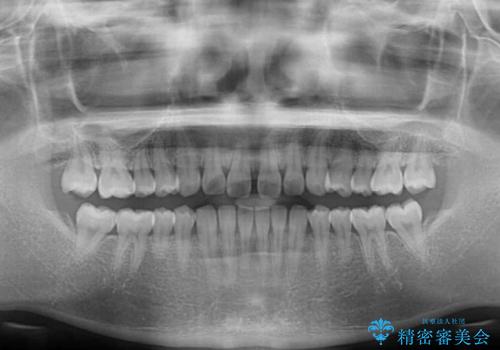

- 上の前歯の隙間を気にして来院された患者様です。

インビザラインにより、隙間を閉じながら、隙間の原因であるディープバイトを改善していくこととしました。

下顎の歯列が強く上顎に咬みこむことで隙間ができてしまうため、マウスピースの保定装置では後戻りのリスクが高くなってしまいます。